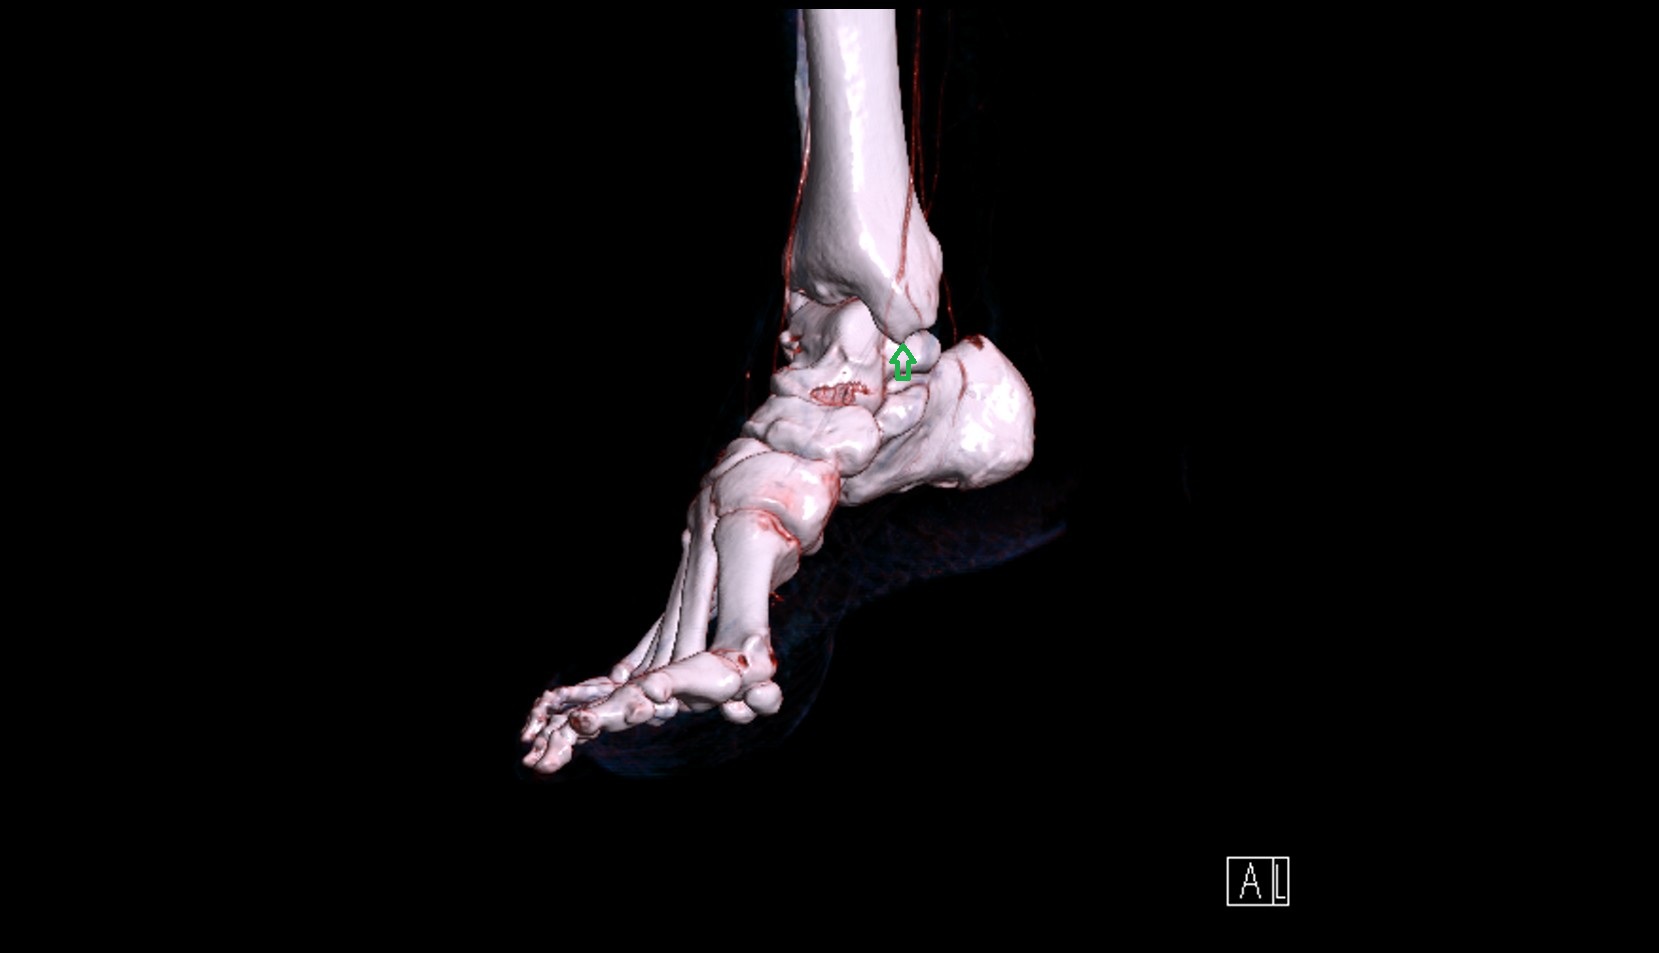

- Ankle joint

- Talus

- Body of talus

- Neck of talus

- Medial malleolus

- Lateral malleolus